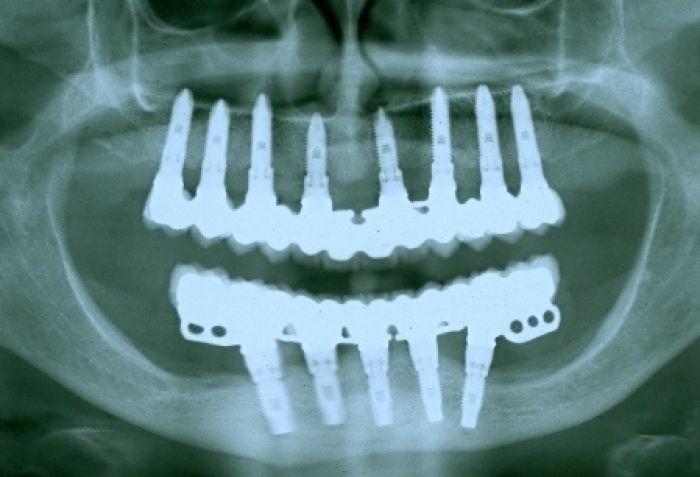

Raio X final

Raio X de 24 meses de controle